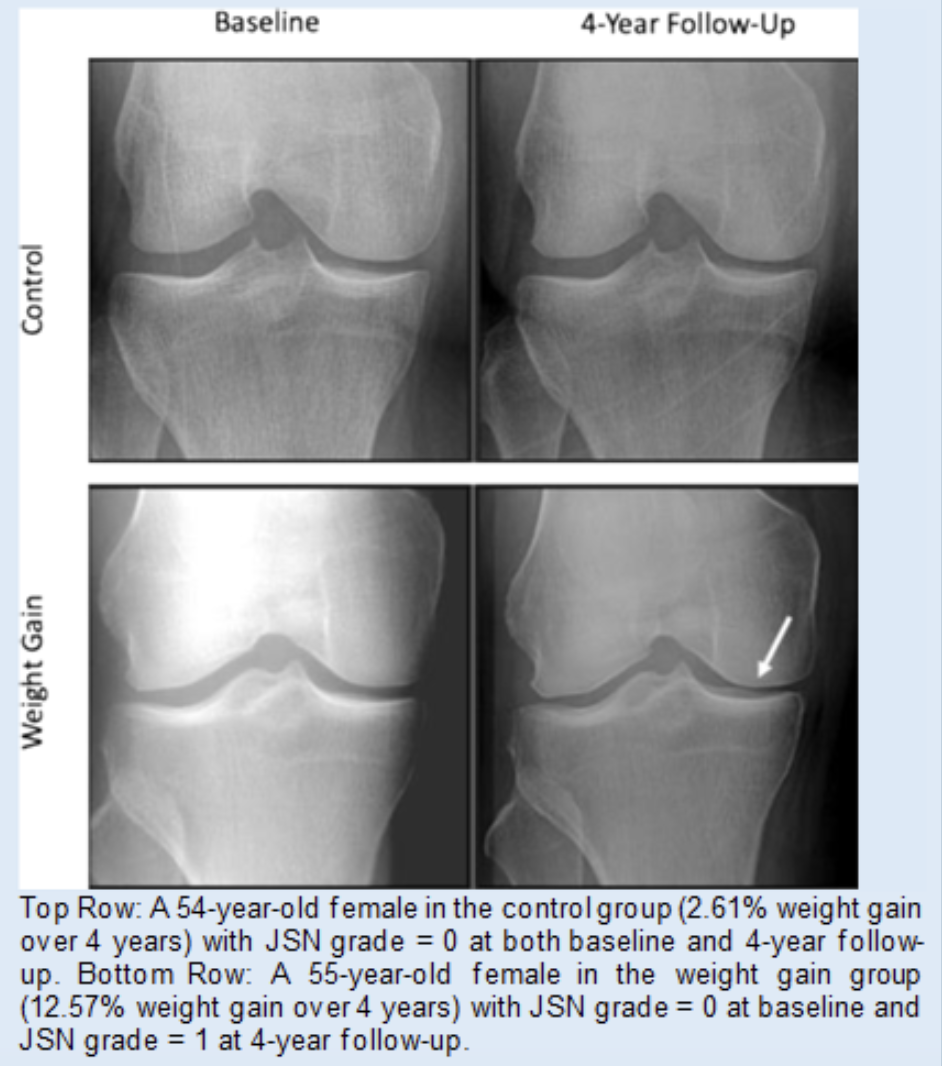

The Clinical and Translational MSK Imaging group (CTMI) uses standard and novel imaging techniques to study abnormalities of the musculoskeletal system. Our focus is on imaging biomarkers in osteoarthritis; the team has developed quantitative and semi-quantitative measurement tools to assess and monitor disease severity. These include Whole-Organ Magnetic Resonance Imaging Scores (WORMS) of the knee, composite scores to measure knee joint synovitis, and the Scoring Hip Osteoarthritis with MRI (SHOMRI) system to study the hip. In addition, artificial intelligence-based tools to measure muscle volume and fat infiltration, periarticular adipose tissue, and synovitis volume have been developed. Recently, we also investigated novel MR imaging techniques to reduce metal artifacts, low field MRI at 0.55T, and CT-like MR imaging techniques.